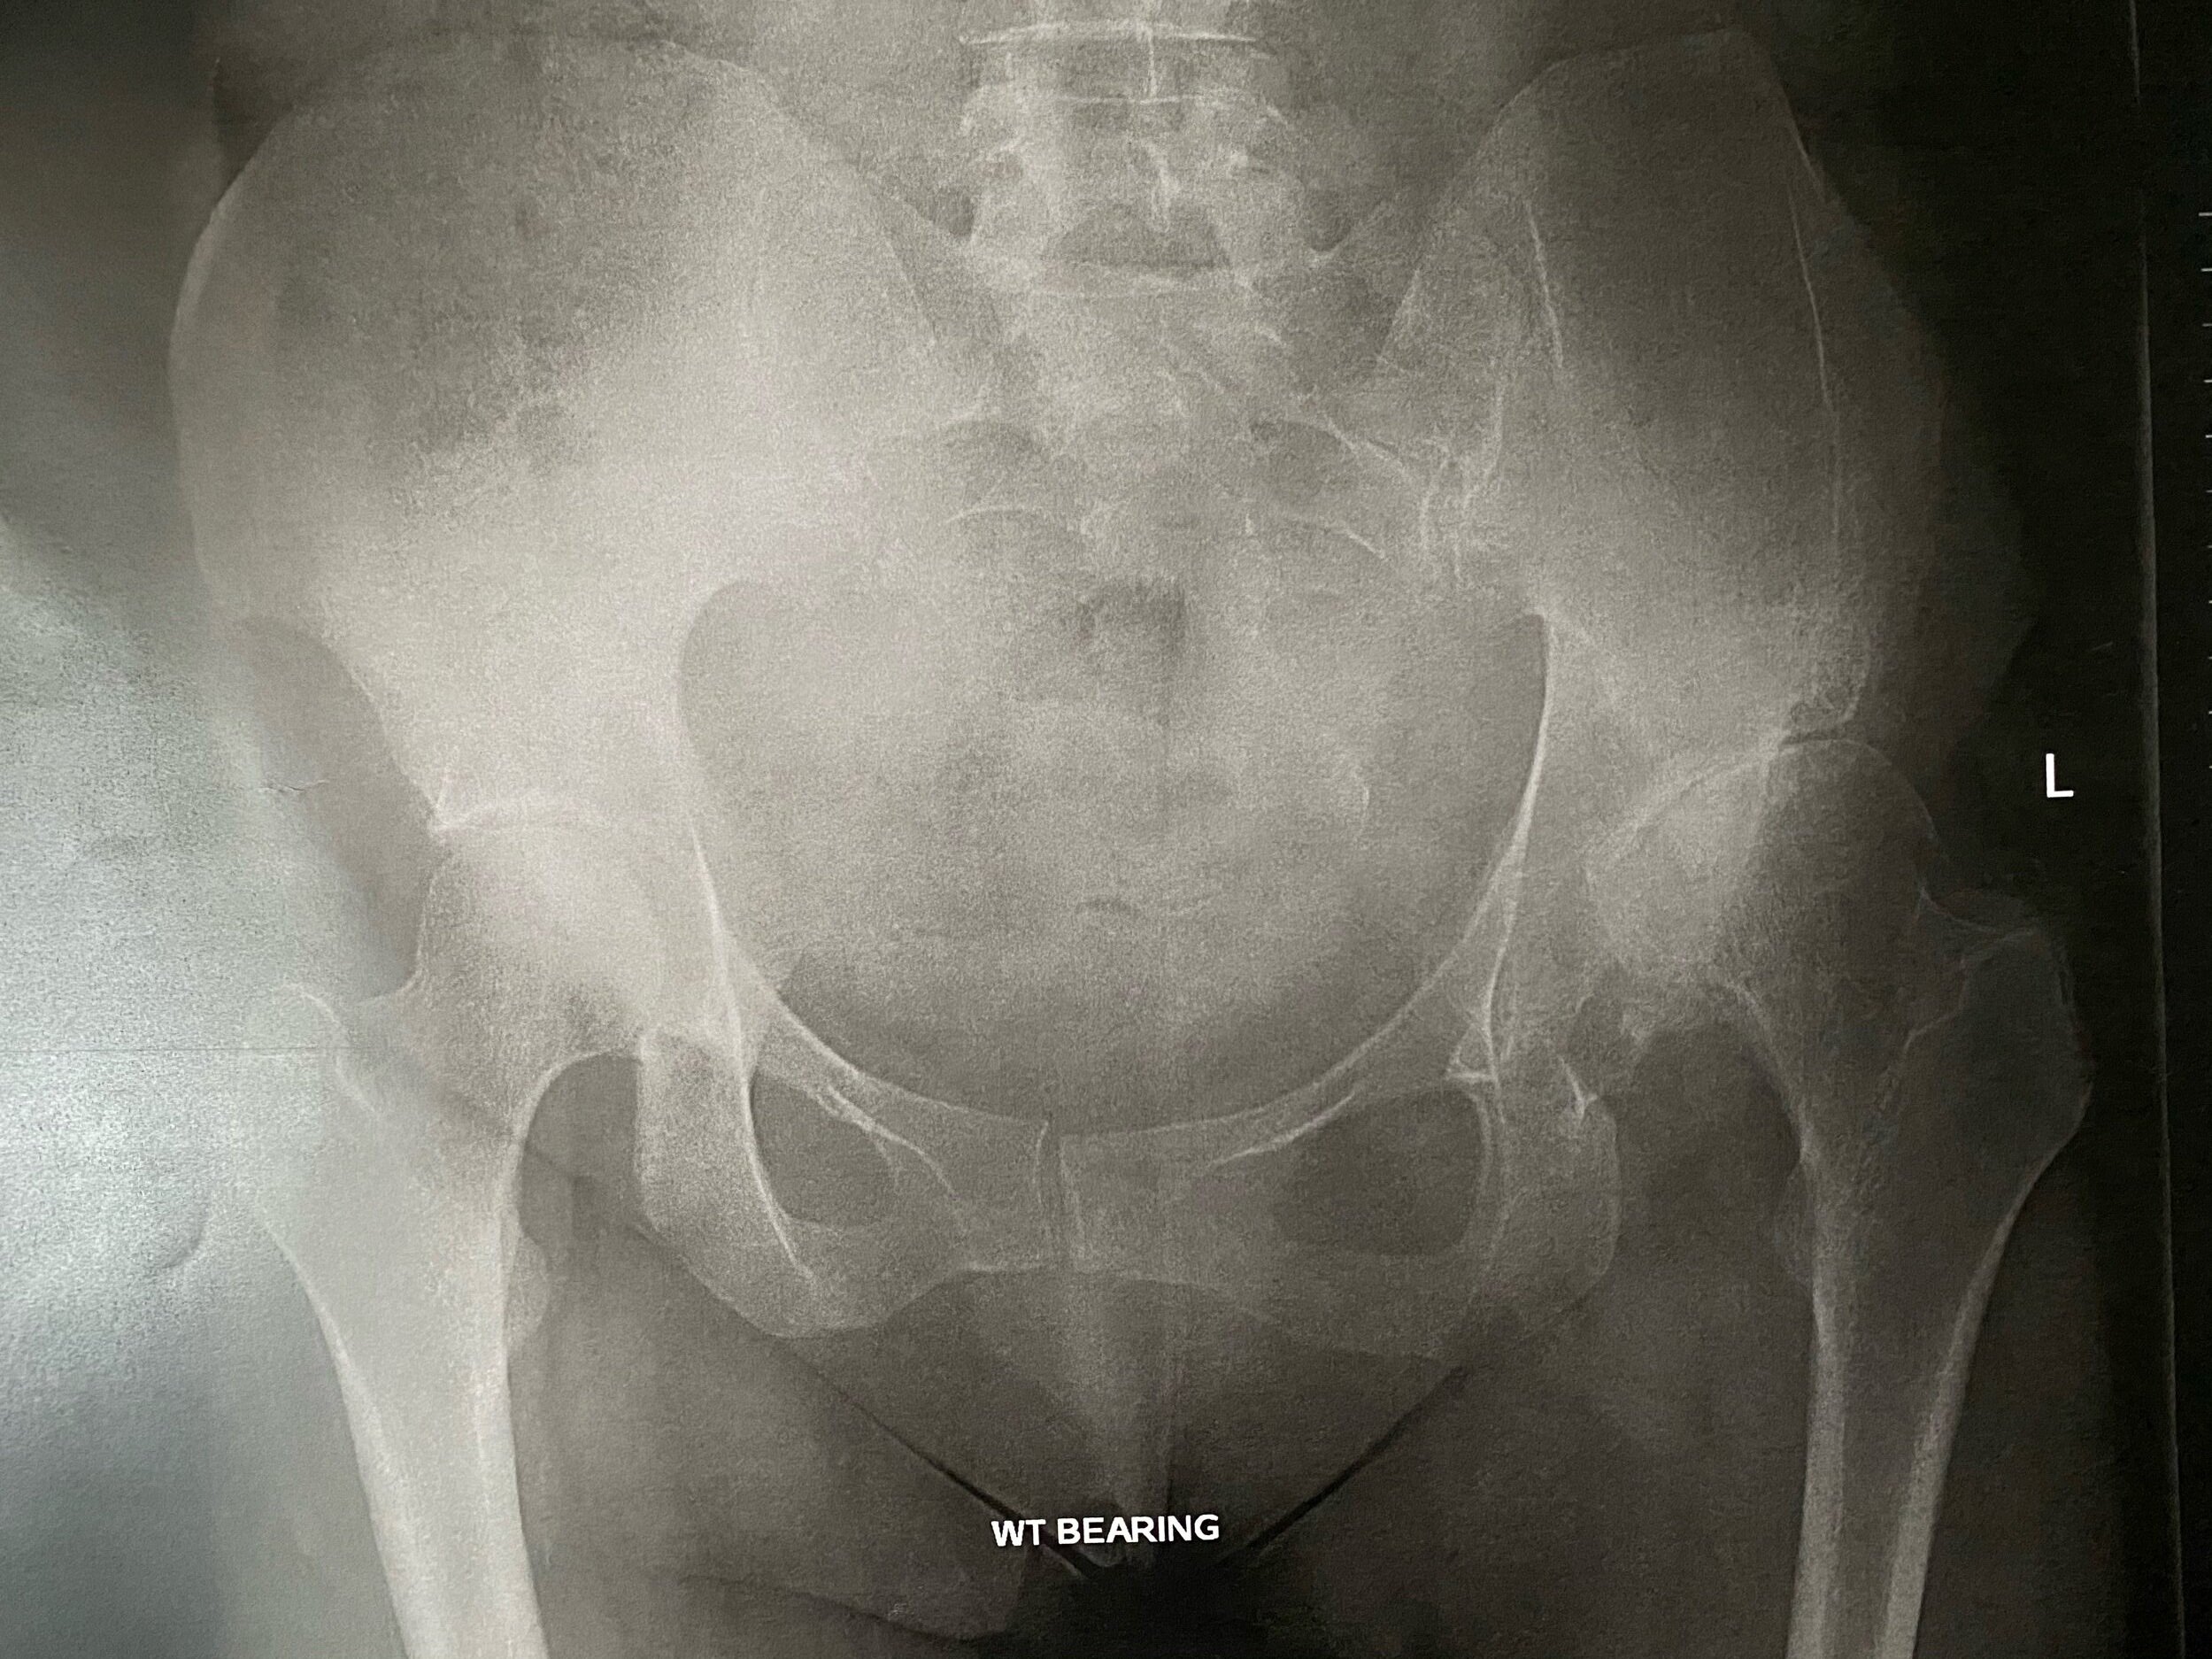

Fast forward to my teens and I would often jump to my feet in the middle of class because I felt like my hip was about to pop out and I was in quite a bit of pain. This lead to another surgery where I was given a bone graft to improve the structure of my hip socket and keep things in place. After this surgery I was in traction for 5 days (similar to that first image above) and on crutches for 3 months. I had for some reason expected this surgery to give me completely normal usage of my hip and at a follow up with a orthopaedic doctor I was basically told to suck it up and that this surgery meant that instead of needing a hip replacement at 25, I now wouldn’t need one until I was 45. So, I sucked it up.

When I took the x-rays above to the surgeon and he assessed me, he told me it was end stage arthritis and that I was definitely a candidate for a total hip replacement. They would be able to operate the following month. I told him I wasn’t ready to book it in yet, which he said was fine but he said “you must be in a lot of pain, I’m sure you won’t want to leave it too long”. And the thing is, I am but I’m not. I have this amazing protocol that keeps me in a pretty manageable state of discomfort, and I know that without this protocol, I would either be in an unbearable amount of pain right now, or I would’ve had the surgery already. I know this because when I stop following my protocol I start to suffer pretty quickly.